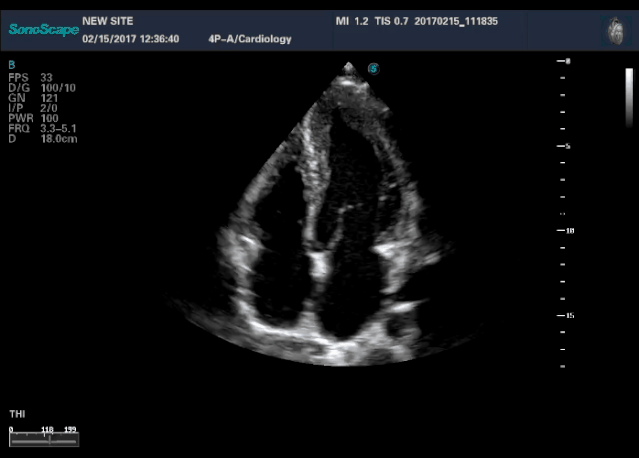

四腔心

(4)转:整个超声探头平面紧贴受检区域皮肤,以超声探头与胸壁的接触点为支点,超声探头以自身中轴线顺时针或逆时针方向旋转一定角度。